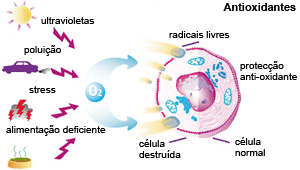

A vitamina C é um antioxidante, ou seja, ajuda a proteger as células contra, os radicais livres, que são moléculas produzidas quando o corpo é exposto algum tipo de “estresse”, além dos naturais como poluição, cigarro, também são formadores de radicais livres o excesso de açúcar, carboidrato, álcool, refrigerantes.

Os radicais livres podem ainda favorecer o surgimento de doenças cardíaca, alguns tipos de câncer, envelhecimento precoce, e outros tipos de doenças.